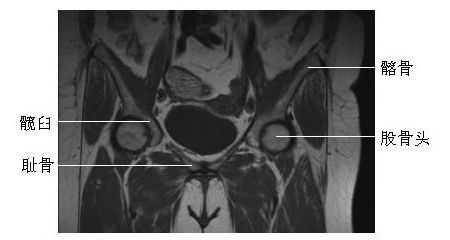

髋关节冠状面(二)